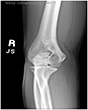

Olecranon Stress Fracture

The patient is an elite baseball pitcher who felt progressive pain in the posterior aspect of his elbow during fall ball. He presented with a stiff shoulder, a diminished arc of motion, and deficiencies in his core musculature. X-rays demonstrated an olecranon stress fracture (far right xray – red arrow). He was shut down from throwing and began to work in physical therapy for his range of motion deficiencies. At two months, the stress fracture showed progression of healing (middle image). By three months, his olecranon stress fracture had healed and he was allowed to begin an interval throwing program (far left xray – red arrow). He returned to pitching at an elite level.